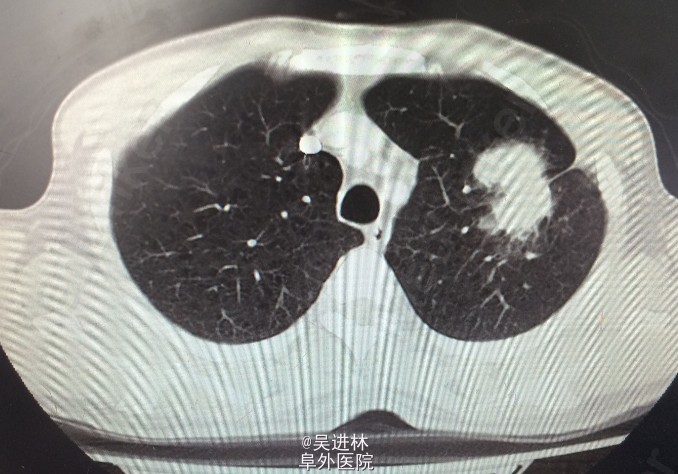

患者男,58岁,主因“咳嗽,体检发现肺部占位5个月。患者5月前无明显诱因出现咳嗽,以夜间为重,遂至外院就诊,行胸部CT检查提示左肺下叶肺不张,伴胸腔积液,纵隔淋巴结轻度肿大;行气管镜检查并取组织病理活检提示为肺鳞状细胞癌。已在我院予以多西他赛+氨磷汀化疗方案治疗,治疗期间未见明显不良反应。患者自发病来,近5个月来体重下降8Kg。

CT:左肺巨大肺癌

诊断:左肺鳞癌 处理:左全肺切除